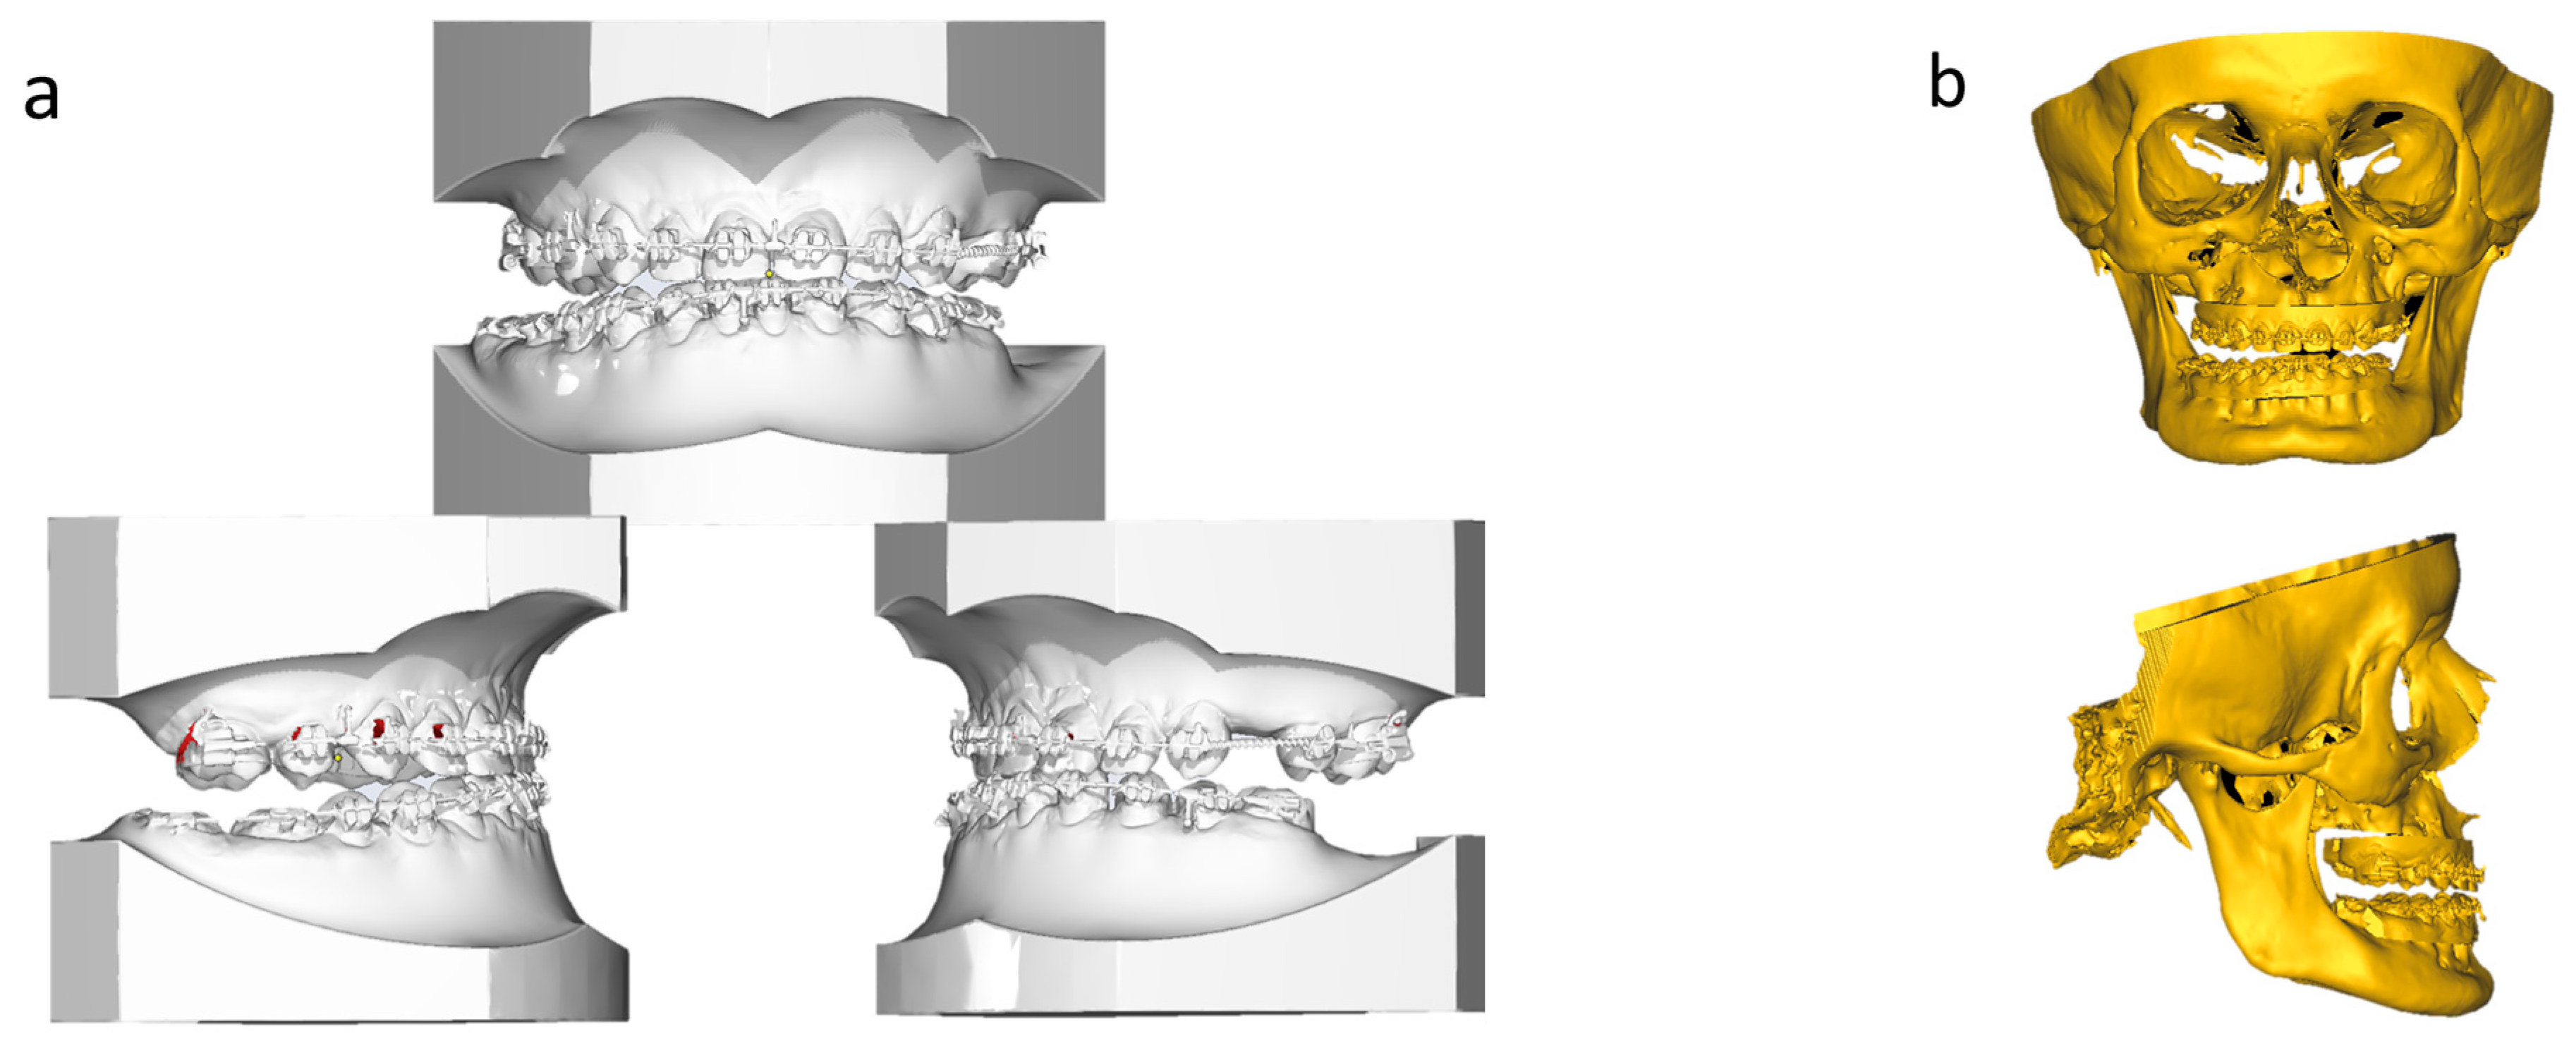

2. Case Report